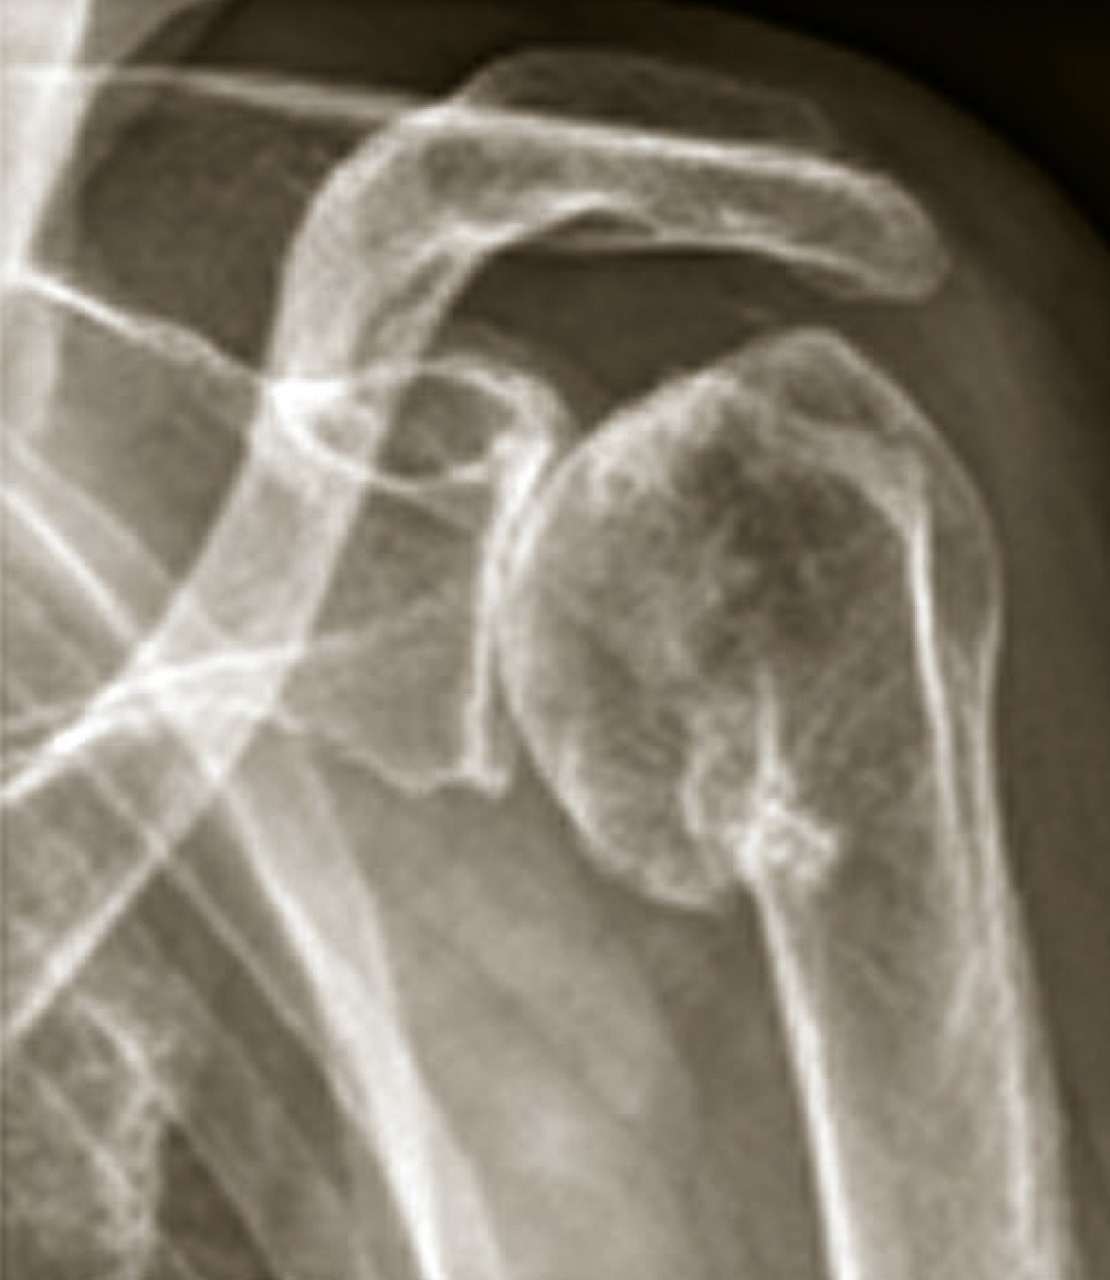

Arthrose de l’épaule (omarthrose)

C’est l’arthrose de l’articulation gléno-humérale. Elle est presque toujours secondaire. On distingue les omarthroses :

• centrées, qui sont primitives ou secondaires à une fracture, une arthrite ou une ostéonécrose (fig. 9) ;

• excentrées, qui sont le plus souvent secondaires à une rupture de la coiffe des rotateurs de l’épaule (fig. 10).

L’omarthrose centrée se manifeste par une ostéophytose céphalique humérale, un espace sous-acromial respecté, un pincement tardif de l’interligne gléno-huméral. Une évolution vers une excentration antéropostérieure avec une subluxation postérieure peut aussi s’observer.

L’omarthrose excentrée se définit par un pincement de l’espace sous-acromial, une arthropathie sous-acromiale avec remodelage du tubercule majeur. Elle peut se compliquer par la constitution d’une néo-­articulation acromio-humérale et une chondrolyse gléno-humérale.